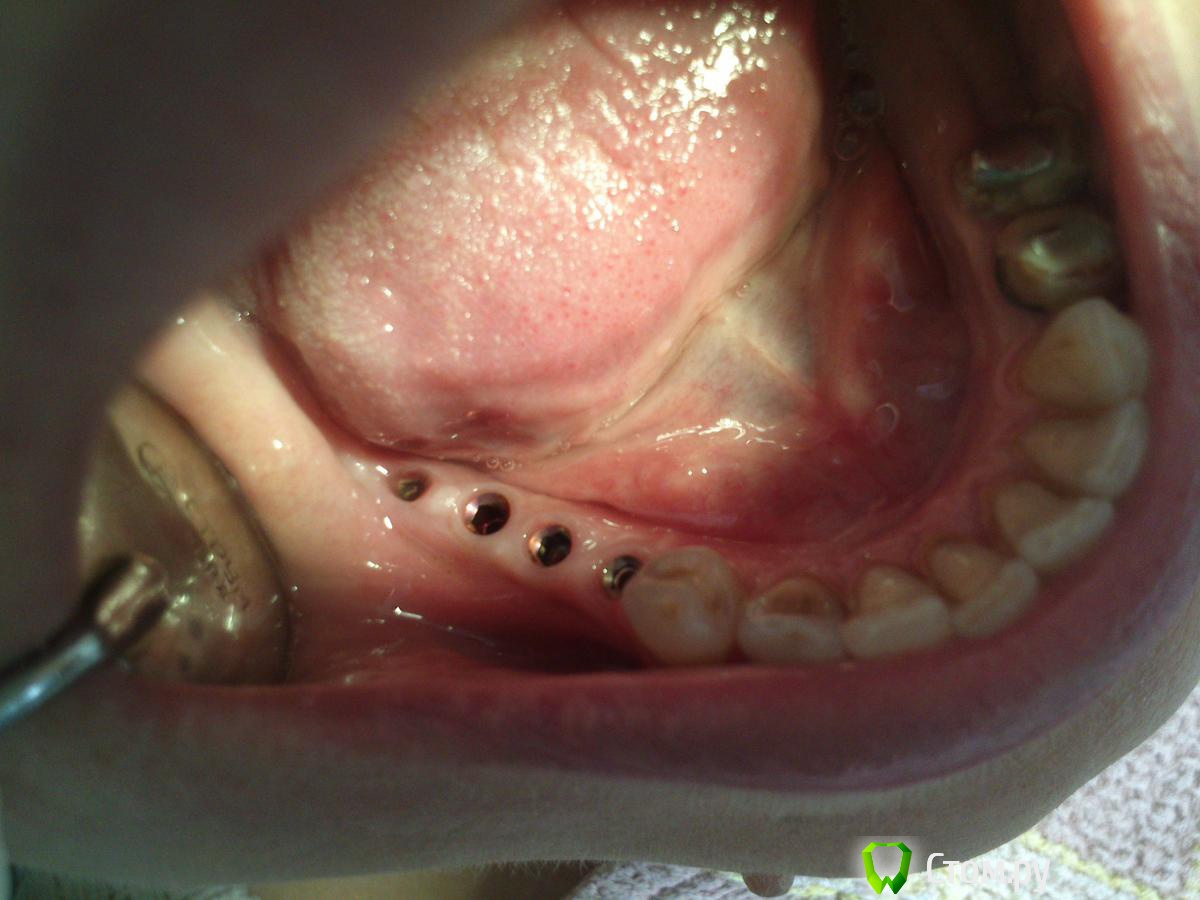

St_Klaus Опубликовано 1 октября, 2014 Поделиться Опубликовано 1 октября, 2014 Фото нет? Хочется на количество десны взглянуть. Ссылка на комментарий

GoDemon Опубликовано 1 октября, 2014 Автор Поделиться Опубликовано 1 октября, 2014 Фото нет? Хочется на количество десны взглянуть.Вот, сегодня специально попросил придти... 1 Ссылка на комментарий